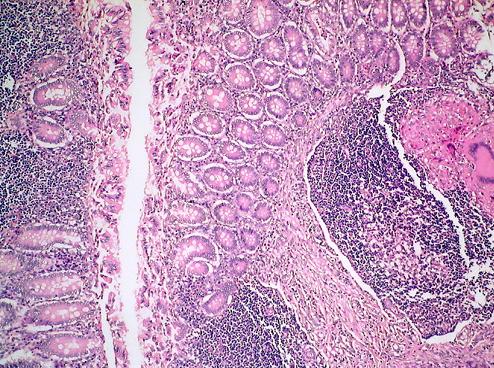

• Creier ramolit, lichefiat; puţinele arii viabile prezintă la nivelul spaţiului subarahnoidian un infiltrat limfoplasmocitar abundent. Acest exudat conţine şi PMN. La nivelul spaţiului Virchow-Robin al arteriolelor ce pătrund în SNC de la nivelul meningelui este prezent, de asemenea, un infiltrat limfoplasmocitar (fig. 3);

• Intestin subțire cu ulcerația focală a mucoasei, cu granuloame tuberculoide coalescente în submucoasă şi extinderea granuloamelor până la nivel seros cu peritonită fibrinoasă. Infiltratul inflamator conține, de asemenea, şi numeroase eozinofile. Coloratia Ziel-Nielson a fost pozitivă, în unele celulele epitelioide din granulom evidențiindu-se bacili. Ficat cu stază cronică şi granuloame de tip tuberculoid miliar la nivel portal. Spaţiile porte prezintă un infiltrat inflamator rotundonuclear şi numeroase eozinofile. Pancreas cu fibroză importantă și dilatare de ducte excretorii (Fig. 6).